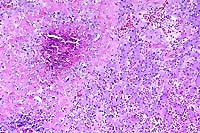

4x

obj.

- Case 23-2. Lymph node. There is a caseating granuloma

displacing cortical lymphocytes which contains foci of mineralization

and giant cells.

20x

- Case 23-2. Lymph node. Partly mineralized caseous

necrotic debris is surrounded by multiple foreign body giant

cells, epithelioid macrophages, lymphocytes, and plasma cells

(tubercle).